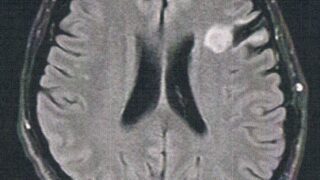

GLIOMA:手術後132ヶ月目の検査

手術から11年が経過した。半年ごとの定期検査です。検査概要びまん性星細胞腫グレード2(悪性転化しやすい腫瘍)MRI検査: 造影剤なし / 造影剤あり造影剤ありの場合:4時間前から絶食し、MRIの1時間前に血液検査を済ませる。診断結果着実に大...